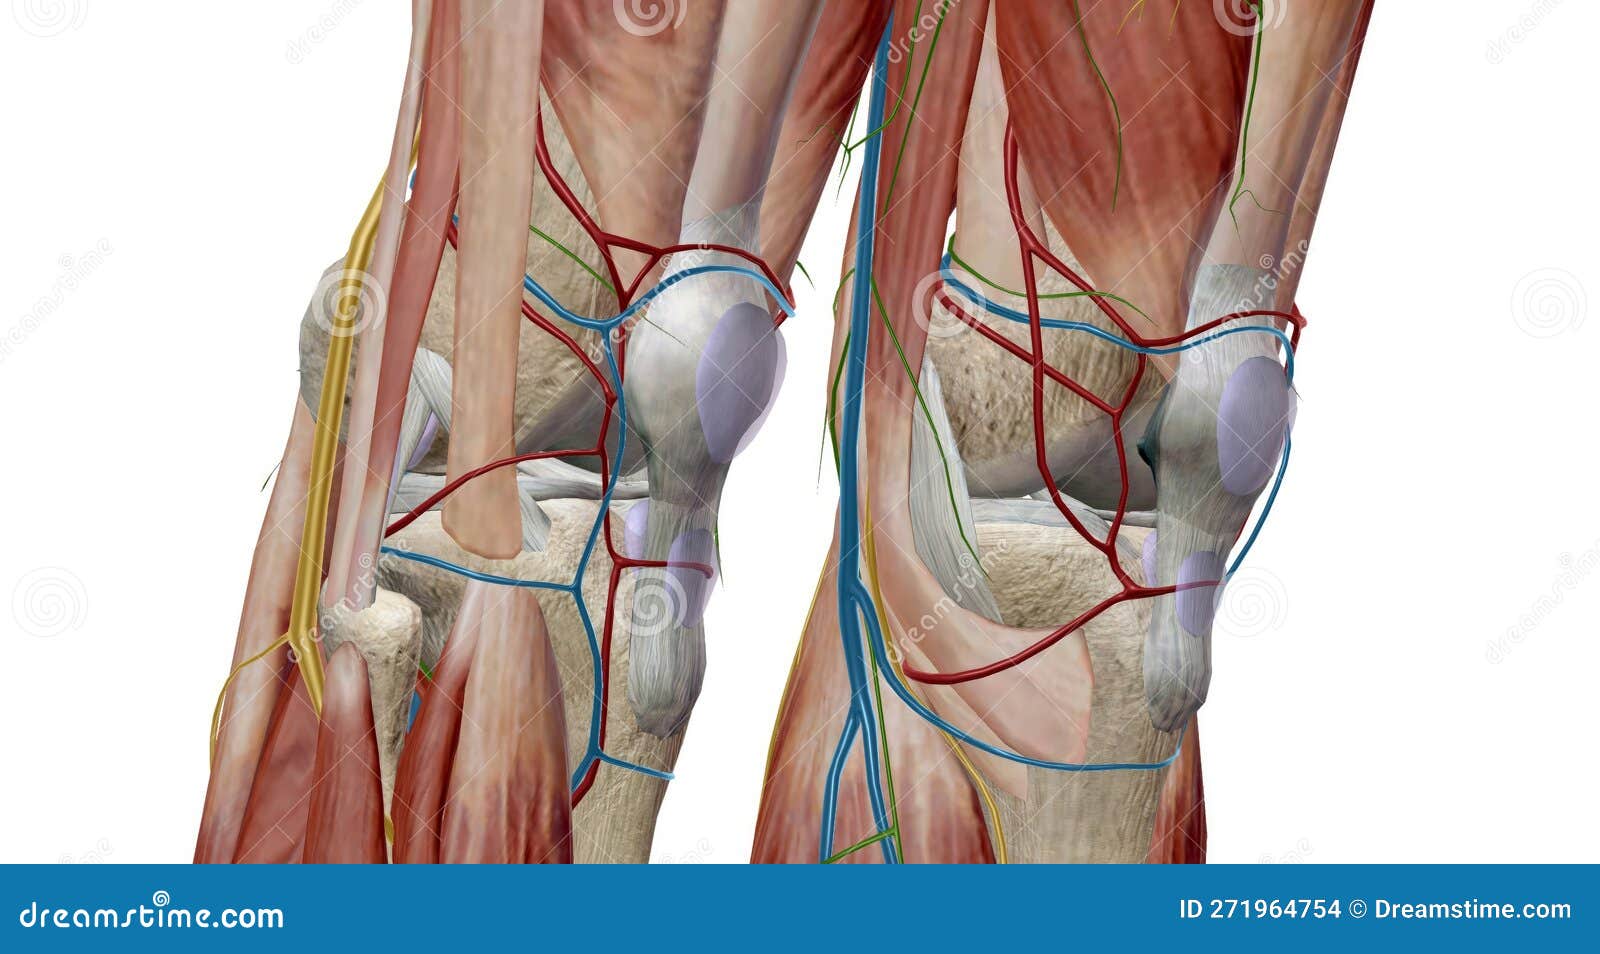

The Knee is the Largest and Most Complex Joint in the Body

The Knee is the Largest and Most Complex Joint in the Body